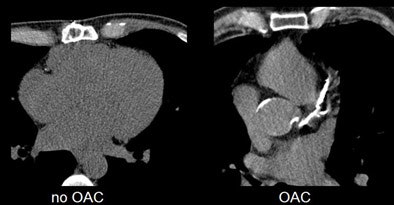

| Compared to non-OAC patient with aortic stenosis (left), typical OAC patient (right) shows extensive aortic and coronary calcium burden. Images courtesy of Dr. Andreas Mahnken. |

The results showed significant differences in coronary calcium burden between the two patient groups. The mean coronary calcium score in patients without OAC was 738 ± 978 versus 1,561 ± 1,141 in patients with long-term OAC (p = 0.024). Similarly, the mean aortic calcium score was 1,070 ± 1,085 in patients without OAC versus 2,410 ± 1,759 in patients with long-term OAC (p = 0.002).